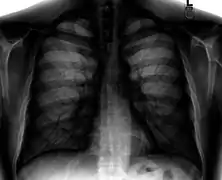

Normal lateral chest radiograph.

Lateral views of the chest are obtained in a similar fashion as the posteroanterior views, except in the lateral view, the patient stands with both arms raised and the left side of the chest pressed against a flat surface.